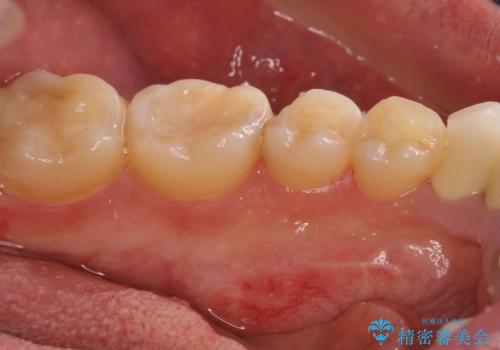

- 張り出している骨隆起による話しにくさを気にして来院された患者様です。

目視でも大きいと分かる骨隆起が認められたため、歯肉を切開した上で切除することとしました。

また、付近の歯に大きなむし歯が認められたため、セラミックインレーによる修復治療も行うこととしました。